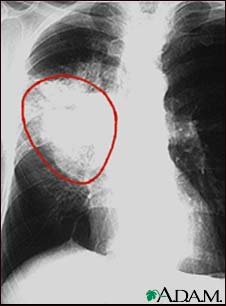

A chest x-ray in a patient with central cancer of the right lung. Notice the white mass in the middle portion of the right lung (seen on the left side of the picture).